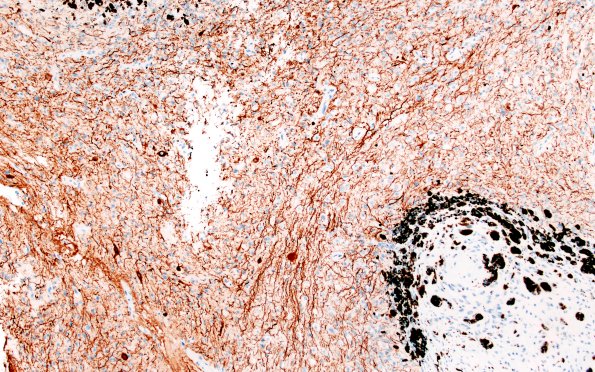

2D1 Pineal Anlage Tumor (Case 2) B5 NF 10X

NF is positive in the larger neurons and neuropil and negative in the neurocytes. (NF IHC)